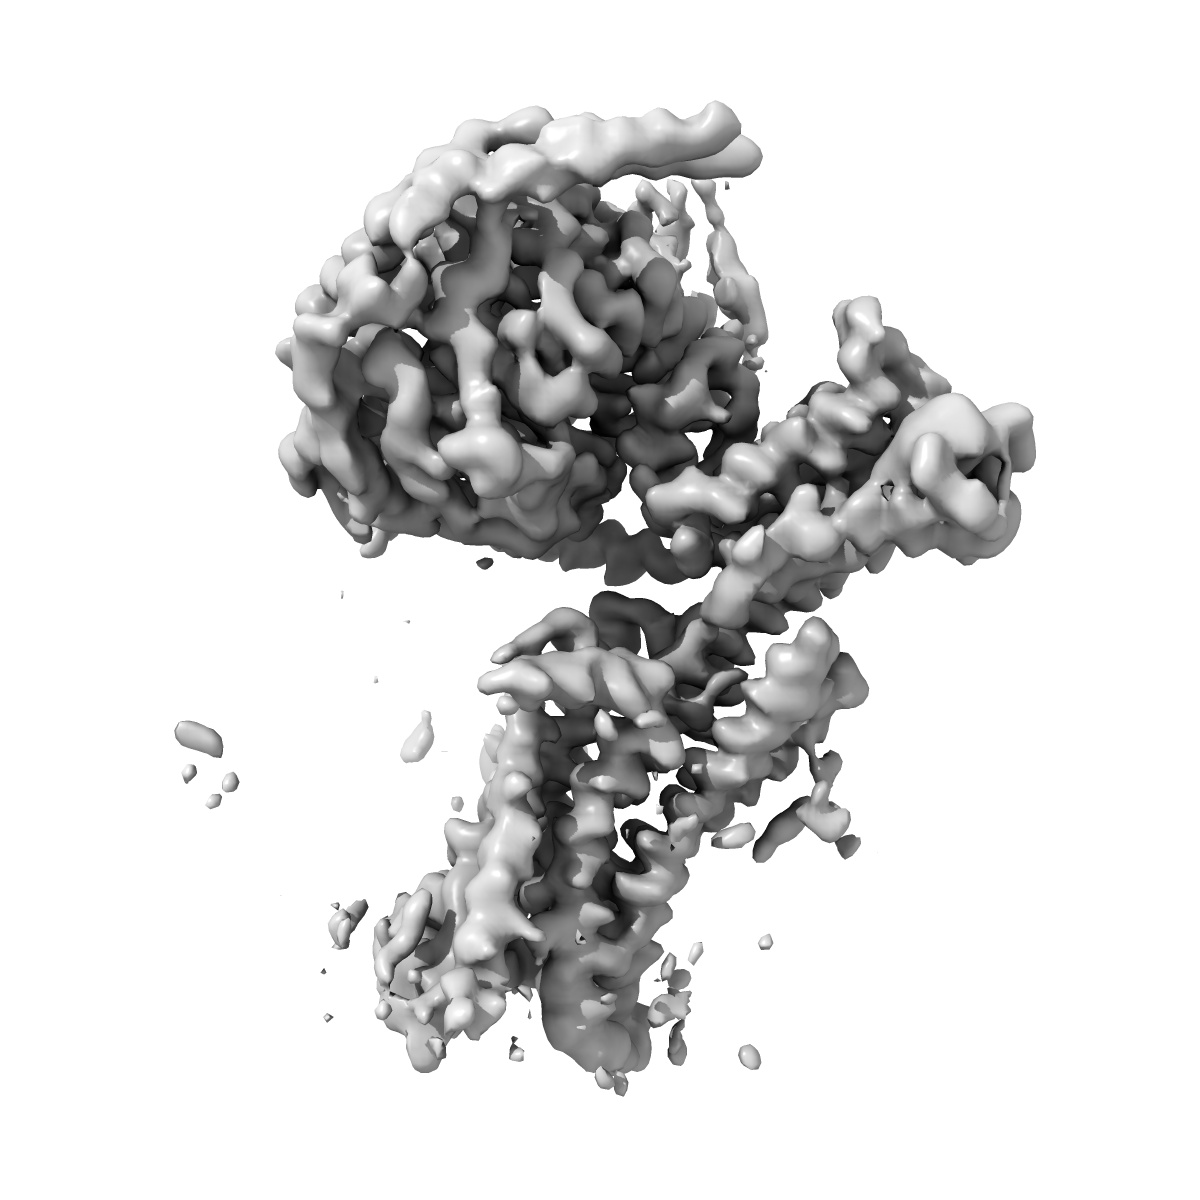

CryoEM structure of D2 dopamine receptor in complex with GoA KE mutant and dopamine

Single-particle3.28 Å

Sample: Human DRD2 in complex with heterotrimeric G protein GoA (K46E) and dopamine

A neurodevelopmental disorder mutation locks G proteins in the transitory pre-activated state.

(2024) Nat Commun , 15 , 6643 - 6643